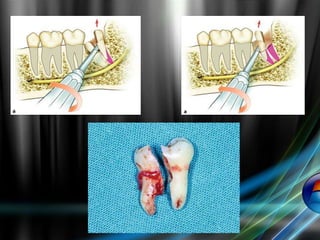

Extraction of Impacted 3rd Molar in Horizontal

Position

2- Delivery of the tooth after tooth division :

Division is indicated to reduce resistance ,create a space or remove

interlocked cusps of the tooth

a- Decapitation:-

Division of the crown of the tooth at cervical margin level .

- indicated in horizontal mandibular and maxillary third molar impaction and

pallataly impacted maxillary cuspid

b- Longitudinal tooth division:

- indicated when the impacted tooth has a widely divergent straight roots,

or when one root is straight and the other is curved

c- Division of the interlocking cusp:

- this is done with mesioangular impaction ,removal of the inter locking

segment of the tooth usually located under the distal surface of 2nd

molar